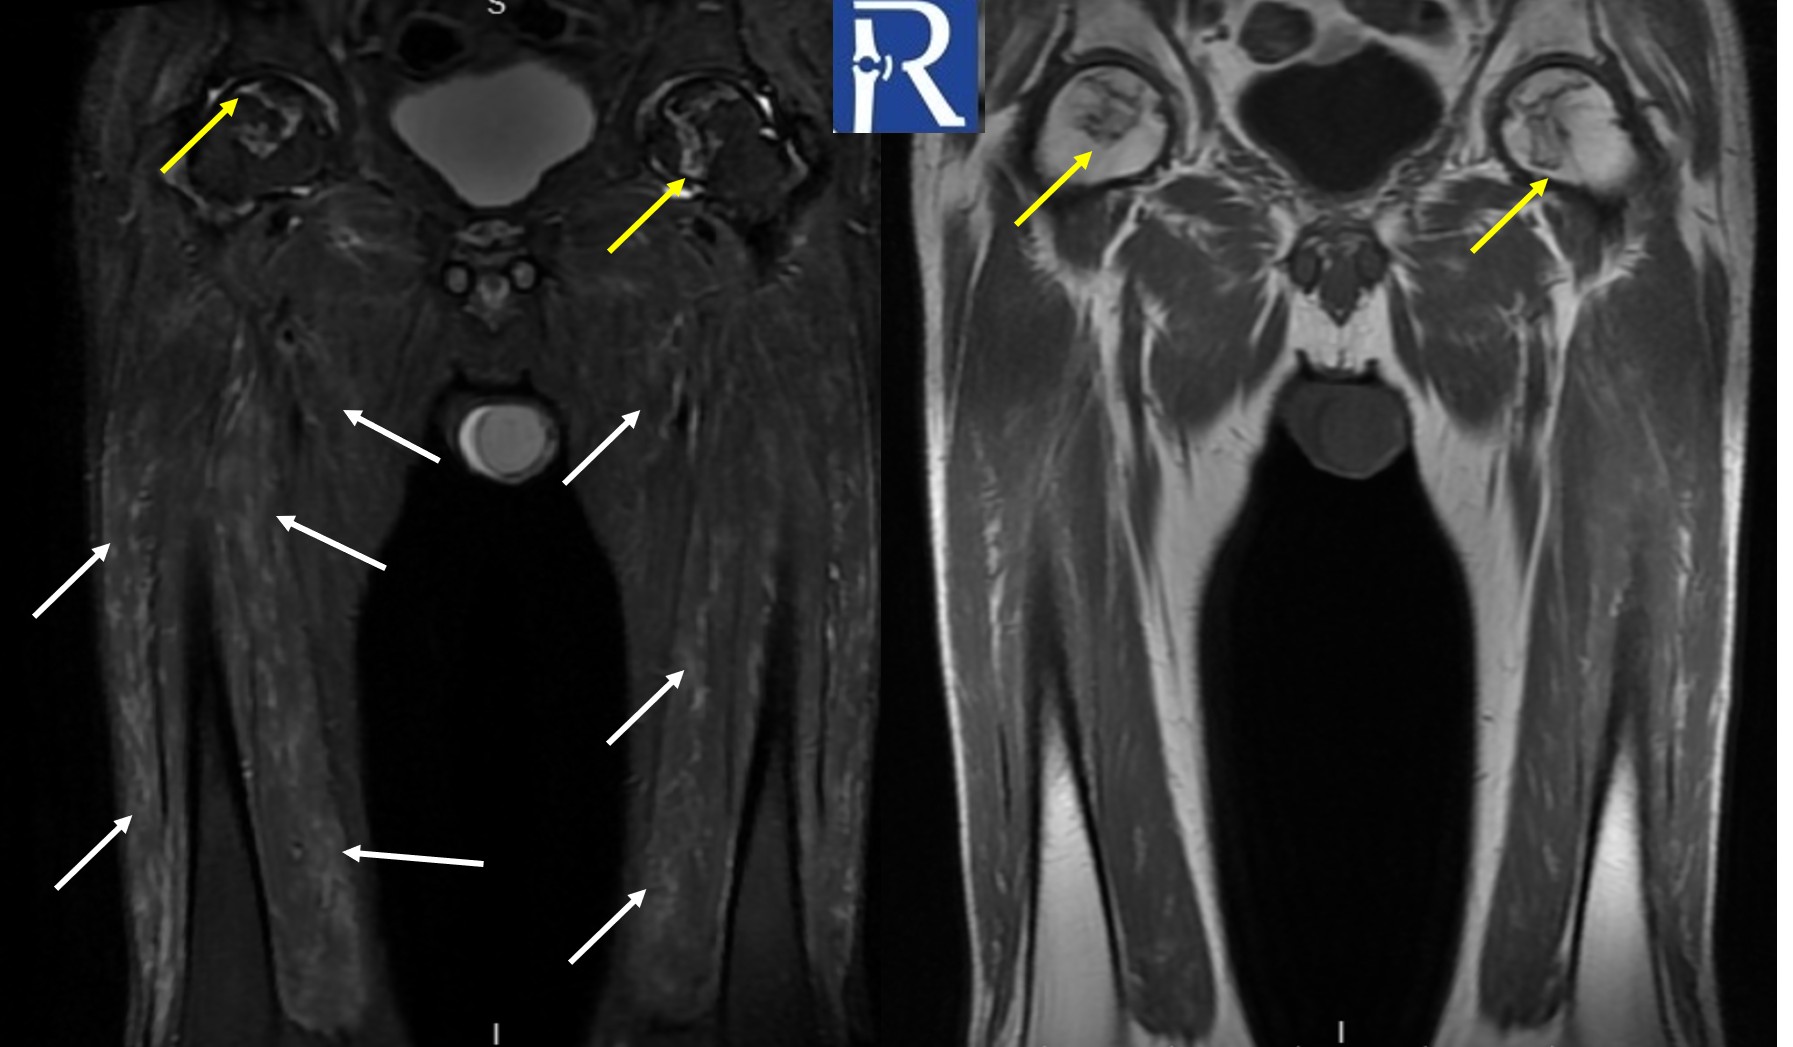

The Forgotten ACL Finding: Stump Entrapment Beyond the Tear in Pivot-Shift Injuries Clinical Context A 46-year-old male presented with acute ...

The arcuate sign is a fibular head avulsion fracture indicating posterolateral corner injury, commonly associated with ACL and PCL tears. Early recogn ...